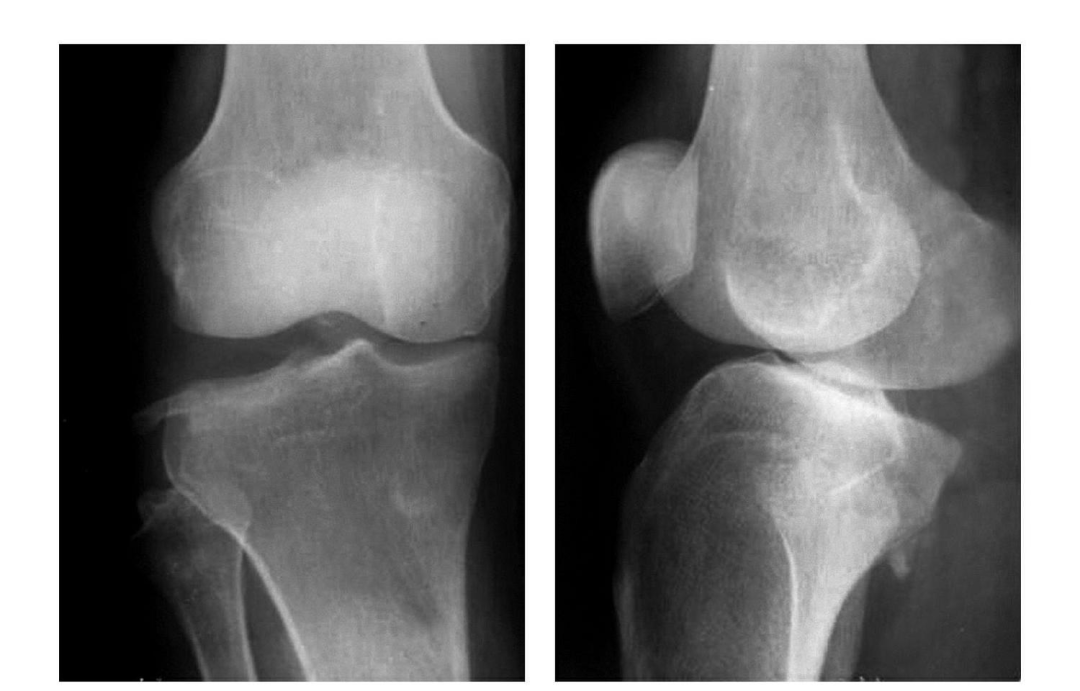

(4)Hoffa 骨折

股骨髁冠状面的骨折称为Hoffa 骨折,Friedrich Busch 在 1869 年首次描述此种类型的骨折,直到 1904 年 Hoffa 详细描述股骨髁外侧髁骨折并命名,随着时间发展,临床上逐渐把股骨内外髁冠状面的骨折都归于 Hoffa 骨折。

Hoffa 骨折属于关节内骨折,常伴髌骨、半月板、交叉韧带、副韧带及胫骨平台的损伤,由于其特殊的解剖结构,此型骨折的发生率极低, 在股骨远端骨折中不足 1%,一般发生在外侧髁。